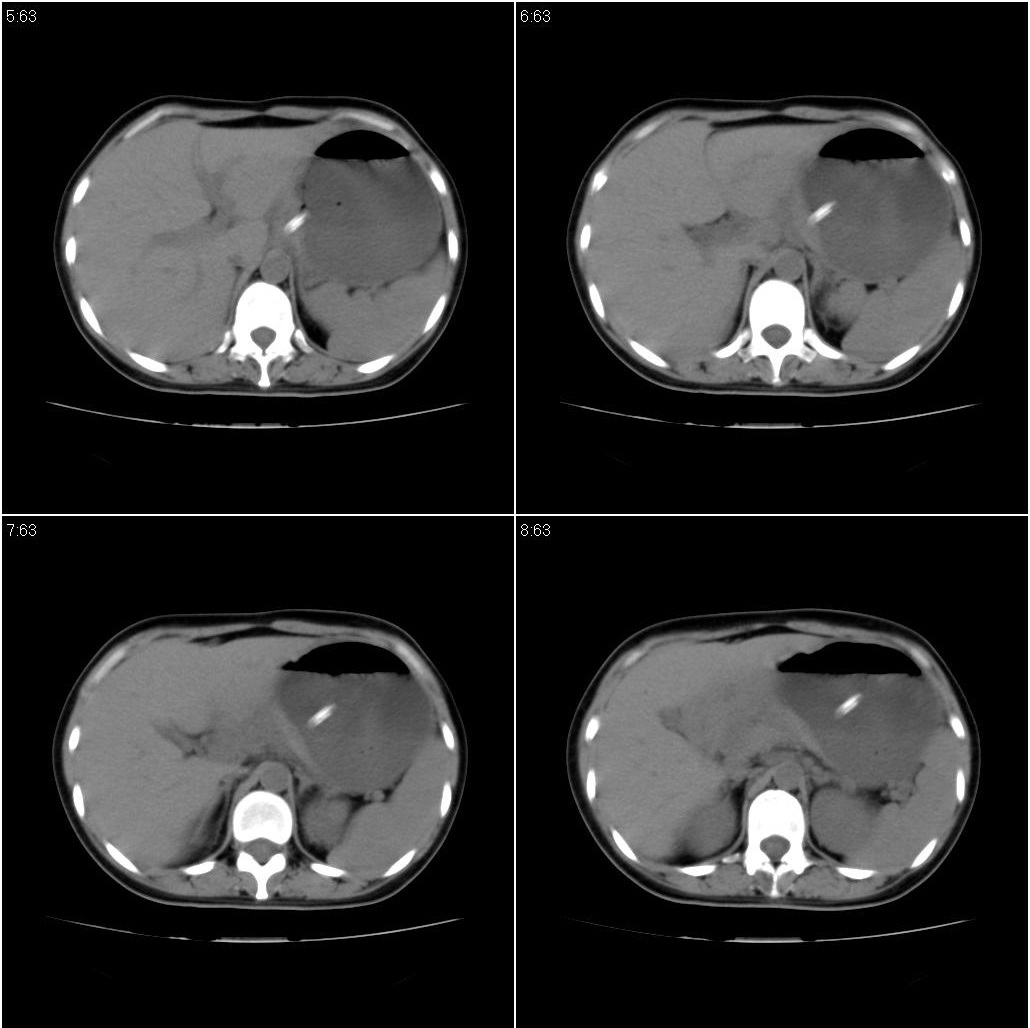

女性,33岁。4个月前因妊娠发现盆腔肿物。ca-125: 1100

胃幽门部癌伴小弯侧和腹腔淋巴结转移,胃内有胃管。

有明显淋巴结吗?我们感觉像是胰腺和胃窦。不过,胰腺尤其是胰头较大,不知道是否正常?

胃窦贲门胃小弯好像都厚啊 ,胃窦处比较明显,而且胃腔扩张明显,考虑胃癌伴梗阻。

未见明显肿大淋巴结,另肝脾大

高密度影是胃肠减压的管子。

支持;胃癌【浸润】幽门梗阻.胰头、胆囊及肝左叶受侵,副脾.

考虑胃窦占位并肝门部淋巴结转移

考虑胃窦部胃癌伴小弯侧和腹腔淋巴结转移。